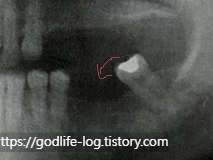

위 사진은 아랫치아를 발치 수 오랫동안 방치하여 맞물리는 치아가 없어서 윗 치아가 정출 된 상황입니다. 반대로 윗 치아가 없으면 아래치아가 위로 솟게 됩니다.

이렇게 치아가 많이 정출 된다면 치아 뿌리가 많이 드러날 수밖에 없고, 최악의 경우에는 윗 치아도 함께 발치를 해야 할 수도 있습니다.